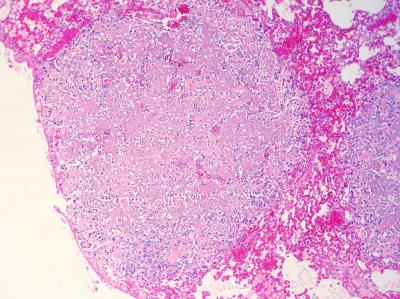

Este estudio retrospectivo fue encaminado por Celic Berenice Montoya, estudiante de especialidad del Departamento de Patología de la Facultad de Veterinaria de la prestigiosa UNAM de México, durante su rotación en Noah's Path en 2017. En el mismo, publicado recientemente en la Revista de Clínica Veterinaria de Pequeños Animales de AVEPA, se describen 6 casos de condrosarcoma en cobayas con predilección por huesos planos y, en 3 de los pacientes, metástasis. Los condrosarcomas se observan en cobayas con mayor frecuencia que en el resto de mamíferos exóticos, en los que son muy raros.